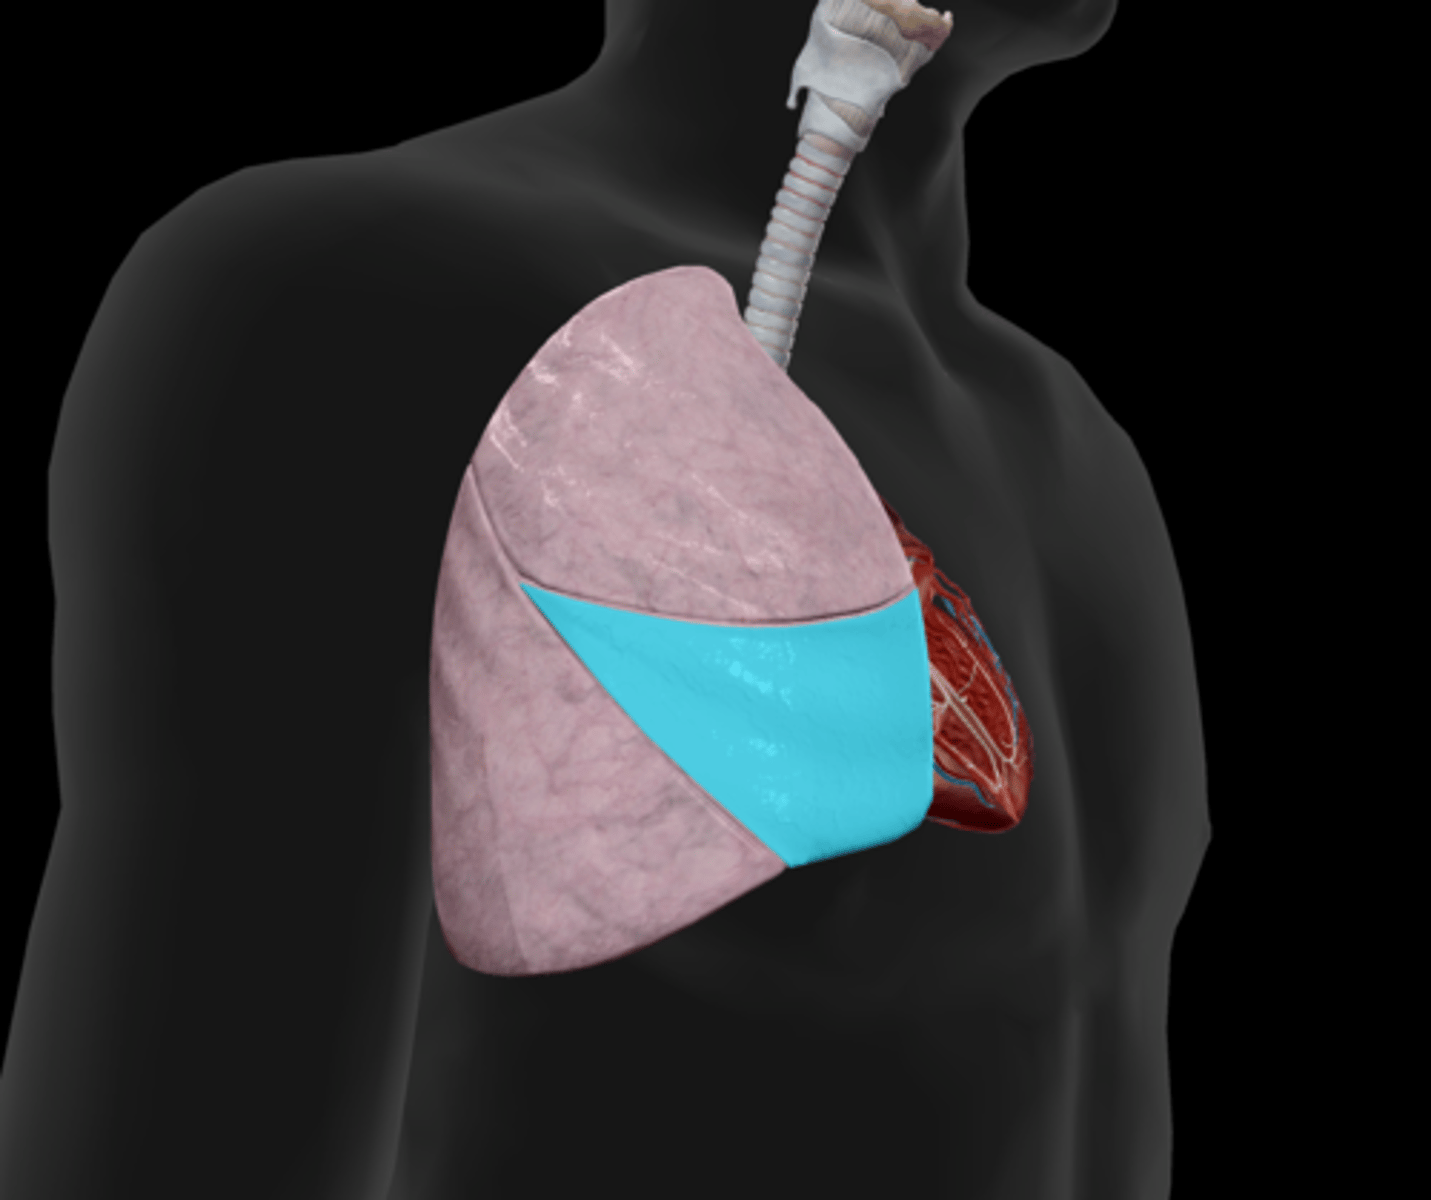

Superior lobe

Middle lobe

Inferior lobe

Horizontal fissure

Oblique fissure